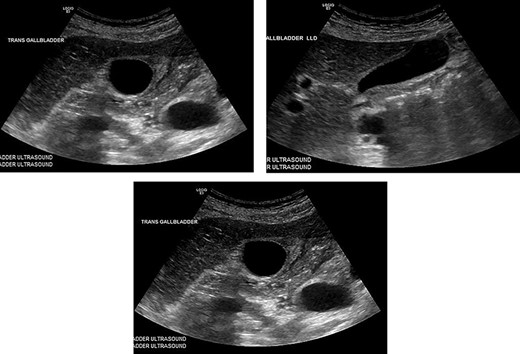

Hematology panel showed a WBC of only 7.6, H&H of 9.0 and 28.9, respectively. BMP was only significant for potassium of 3.4, all other values were normal. The patient had an RUQ ultrasound showing a thickened gall bladder wall at 4.5 mm, small amount of pericholecystic fluid. There were no gallstones and the common bile duct was within normal caliber (Figs 1–3).

These are from the patient’s ultrasound in the ER. The gall bladder wall was measured at 4.5 mm, and a small amount of pericholecystic fluid was present. There were no gallstones and the common bile duct was within normal caliber.